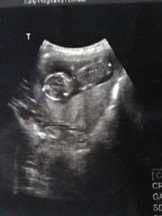

13+1 ตัวเล็กมั้ยครับ

ฝากตัวน้อยไว้ด้วยนะครีบ